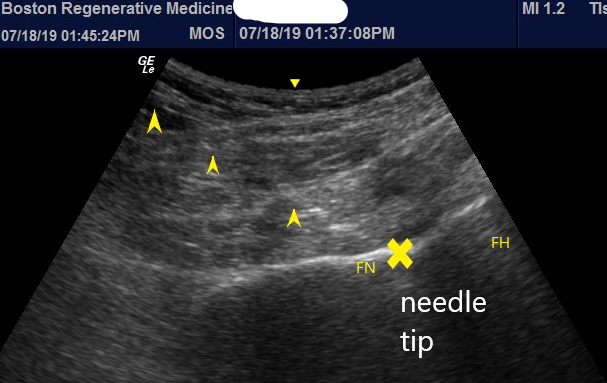

Fig 2a

Hey, Ultrasound! What Did I Do Without You?